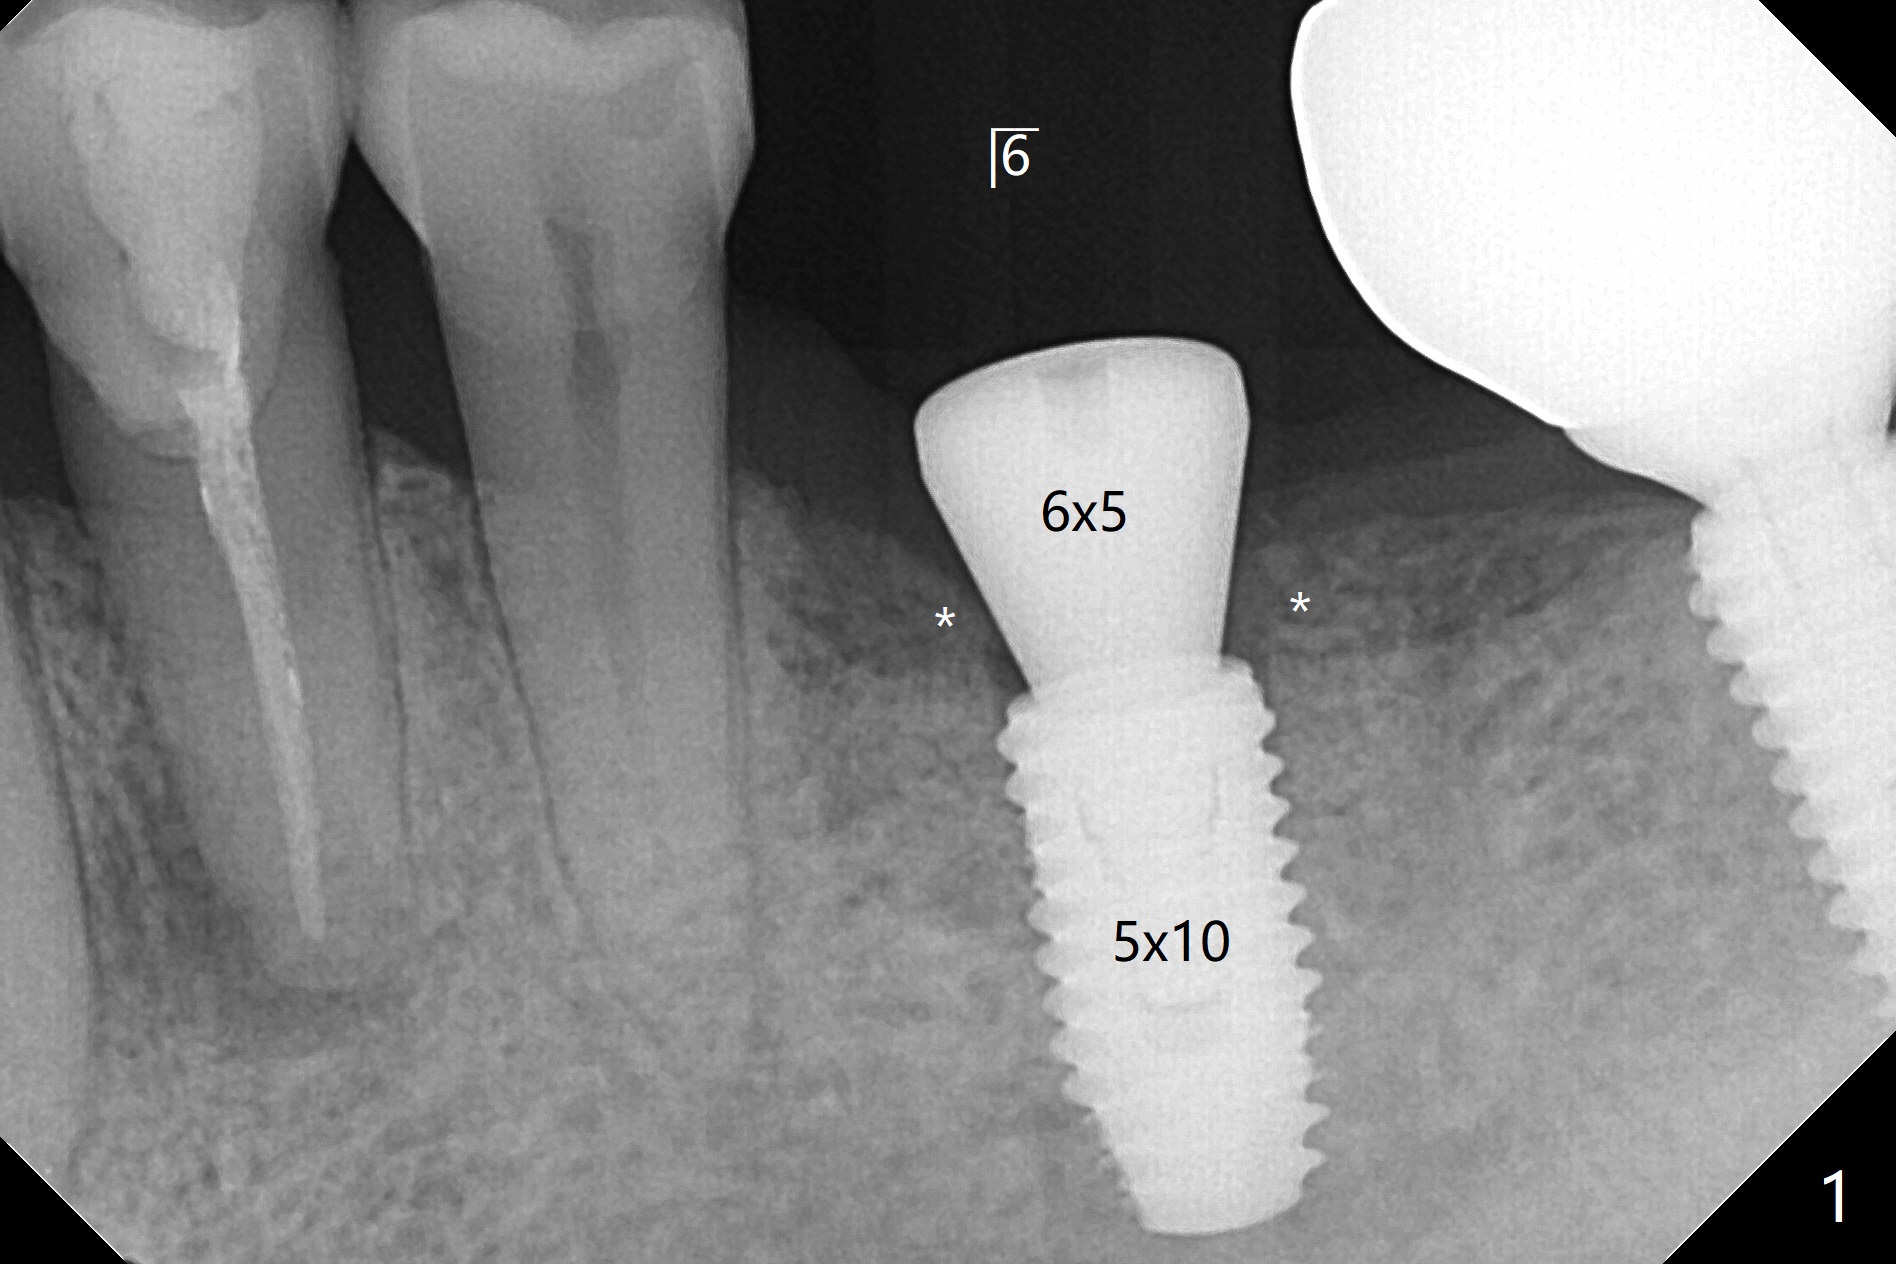

左下6位点保留11个月,病人回来做导板种植,由于骨质硬,必须使用5毫米攻螺纹钻头以及5毫米皮质骨钻头,反复多次倒旋植体,最后勉勉强强扭力不超过40Ncm。否则手术顺利,不翻瓣,角化龈宽,而今天另外两个病例(左上6,左下7)事先没有做位点保存,需要翻瓣植骨,费时吃力。虽然愈合基台似乎完全就位,但是接近近中,远中牙槽嵴(图一:*),去除后,使用6毫米profile钻头,再次放置。术后病人没有任何不适。术后6.5月,基台完全就位,与没有牙槽嵴阻挡有关(图二)。骨质密度高,植入扭力高,没有造成骨质吸收。